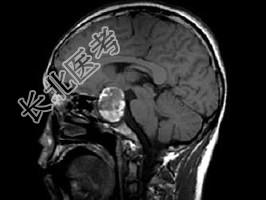

- 单项选择题男,26岁, 突发性视力障碍3天,根据所提供图像, 最可能的诊断为 ( )

D、嫌色细胞瘤(垂体瘤卒中)